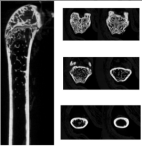

皮质骨 | 皮质骨总面积 | Tt.Ar | mm2 | ||||

皮质骨面积 | Ct.Ar | mm2 | |||||

皮质骨厚度 | Ct.Th | μm | |||||

皮质骨面积与总面积的比值 | Ct.Ar/ Tt.Ar | % | |||||

骨髓腔面积 | Ma.Ar | mm2 | |||||

皮质骨参数 | 皮质骨总面积(Tt.Ar) | 皮质骨面积(Ct.Ar) | 皮质骨厚度(Ct.Th) |

皮质骨面积与总面积比值(Ct.Ar/ Tt.Ar) | 骨体积(Ct.BV) | 组织矿物质含量(Ct.TMC) | |

组织矿物质密度(Ct.TMD) | 骨髓腔区域面积(Ma.Ar) | ||